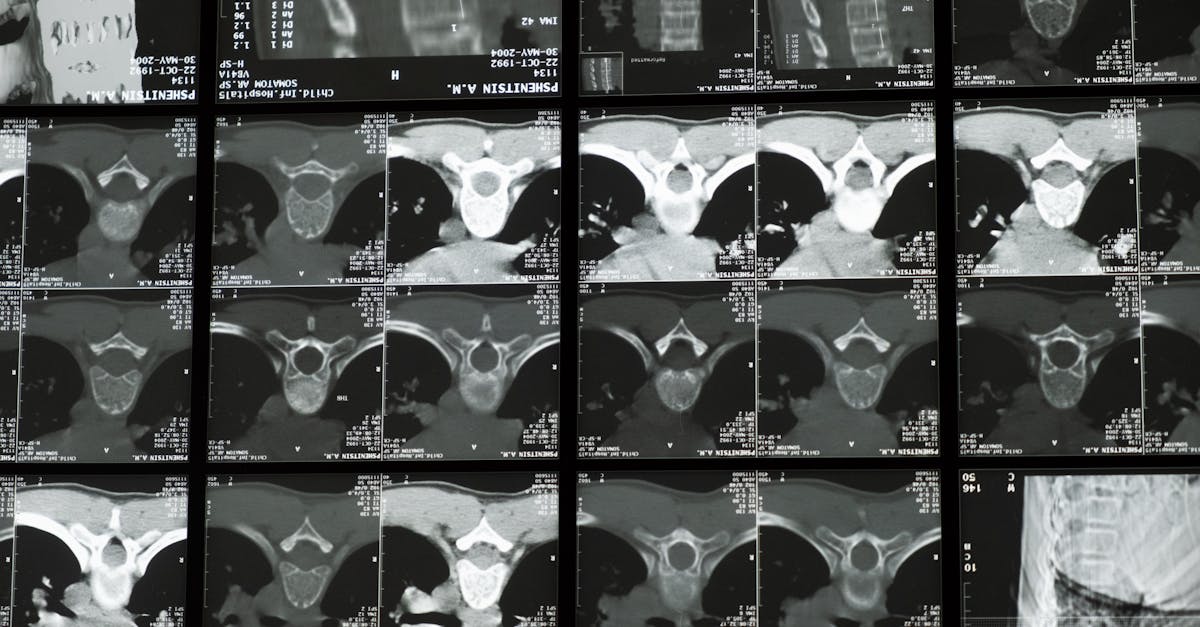

scoliose . Le lien entre la posture, la santé de la colonne vertébrale et la scoliose est crucial, car la façon dont nous nous tenons debout, assis et bougeons est profondément liée à l’alignement de notre colonne vertébrale. Des exercices spécifiques peuvent aider les individus à se tenir plus droit tout en renforçant les muscles autour de leur colonne vertébrale, en particulier au niveau des épaules. Le

Méthode Schroth , une approche de physiothérapie, propose des exercices sur mesure pour les personnes atteintes de scoliose en se concentrant sur la courbure individuelle de la colonne vertébrale. Intégrer des stratégies efficaces pourtraiter les hanches inégales